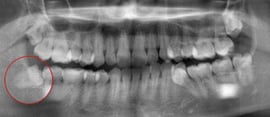

右下の親知らずが度々腫れるとのことで来院された状態です。 手前の歯にロックされていて横に向いている親知らずが生えることができません。

お口の中を一旦きれいに清掃し、お薬にて腫れを落ち着かせた状態にしてから親知らずを抜歯します。

平均しておおよそ10分~20分程度の処置時間です。